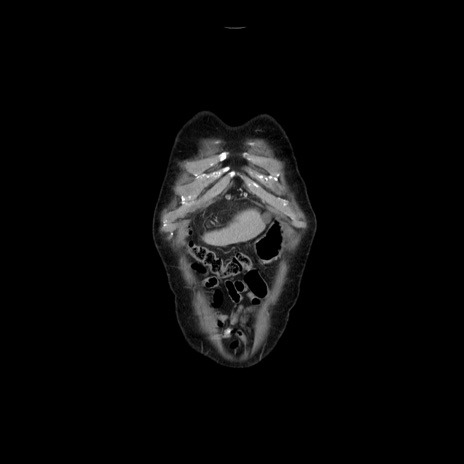

症例21(冠状断像)

横断像